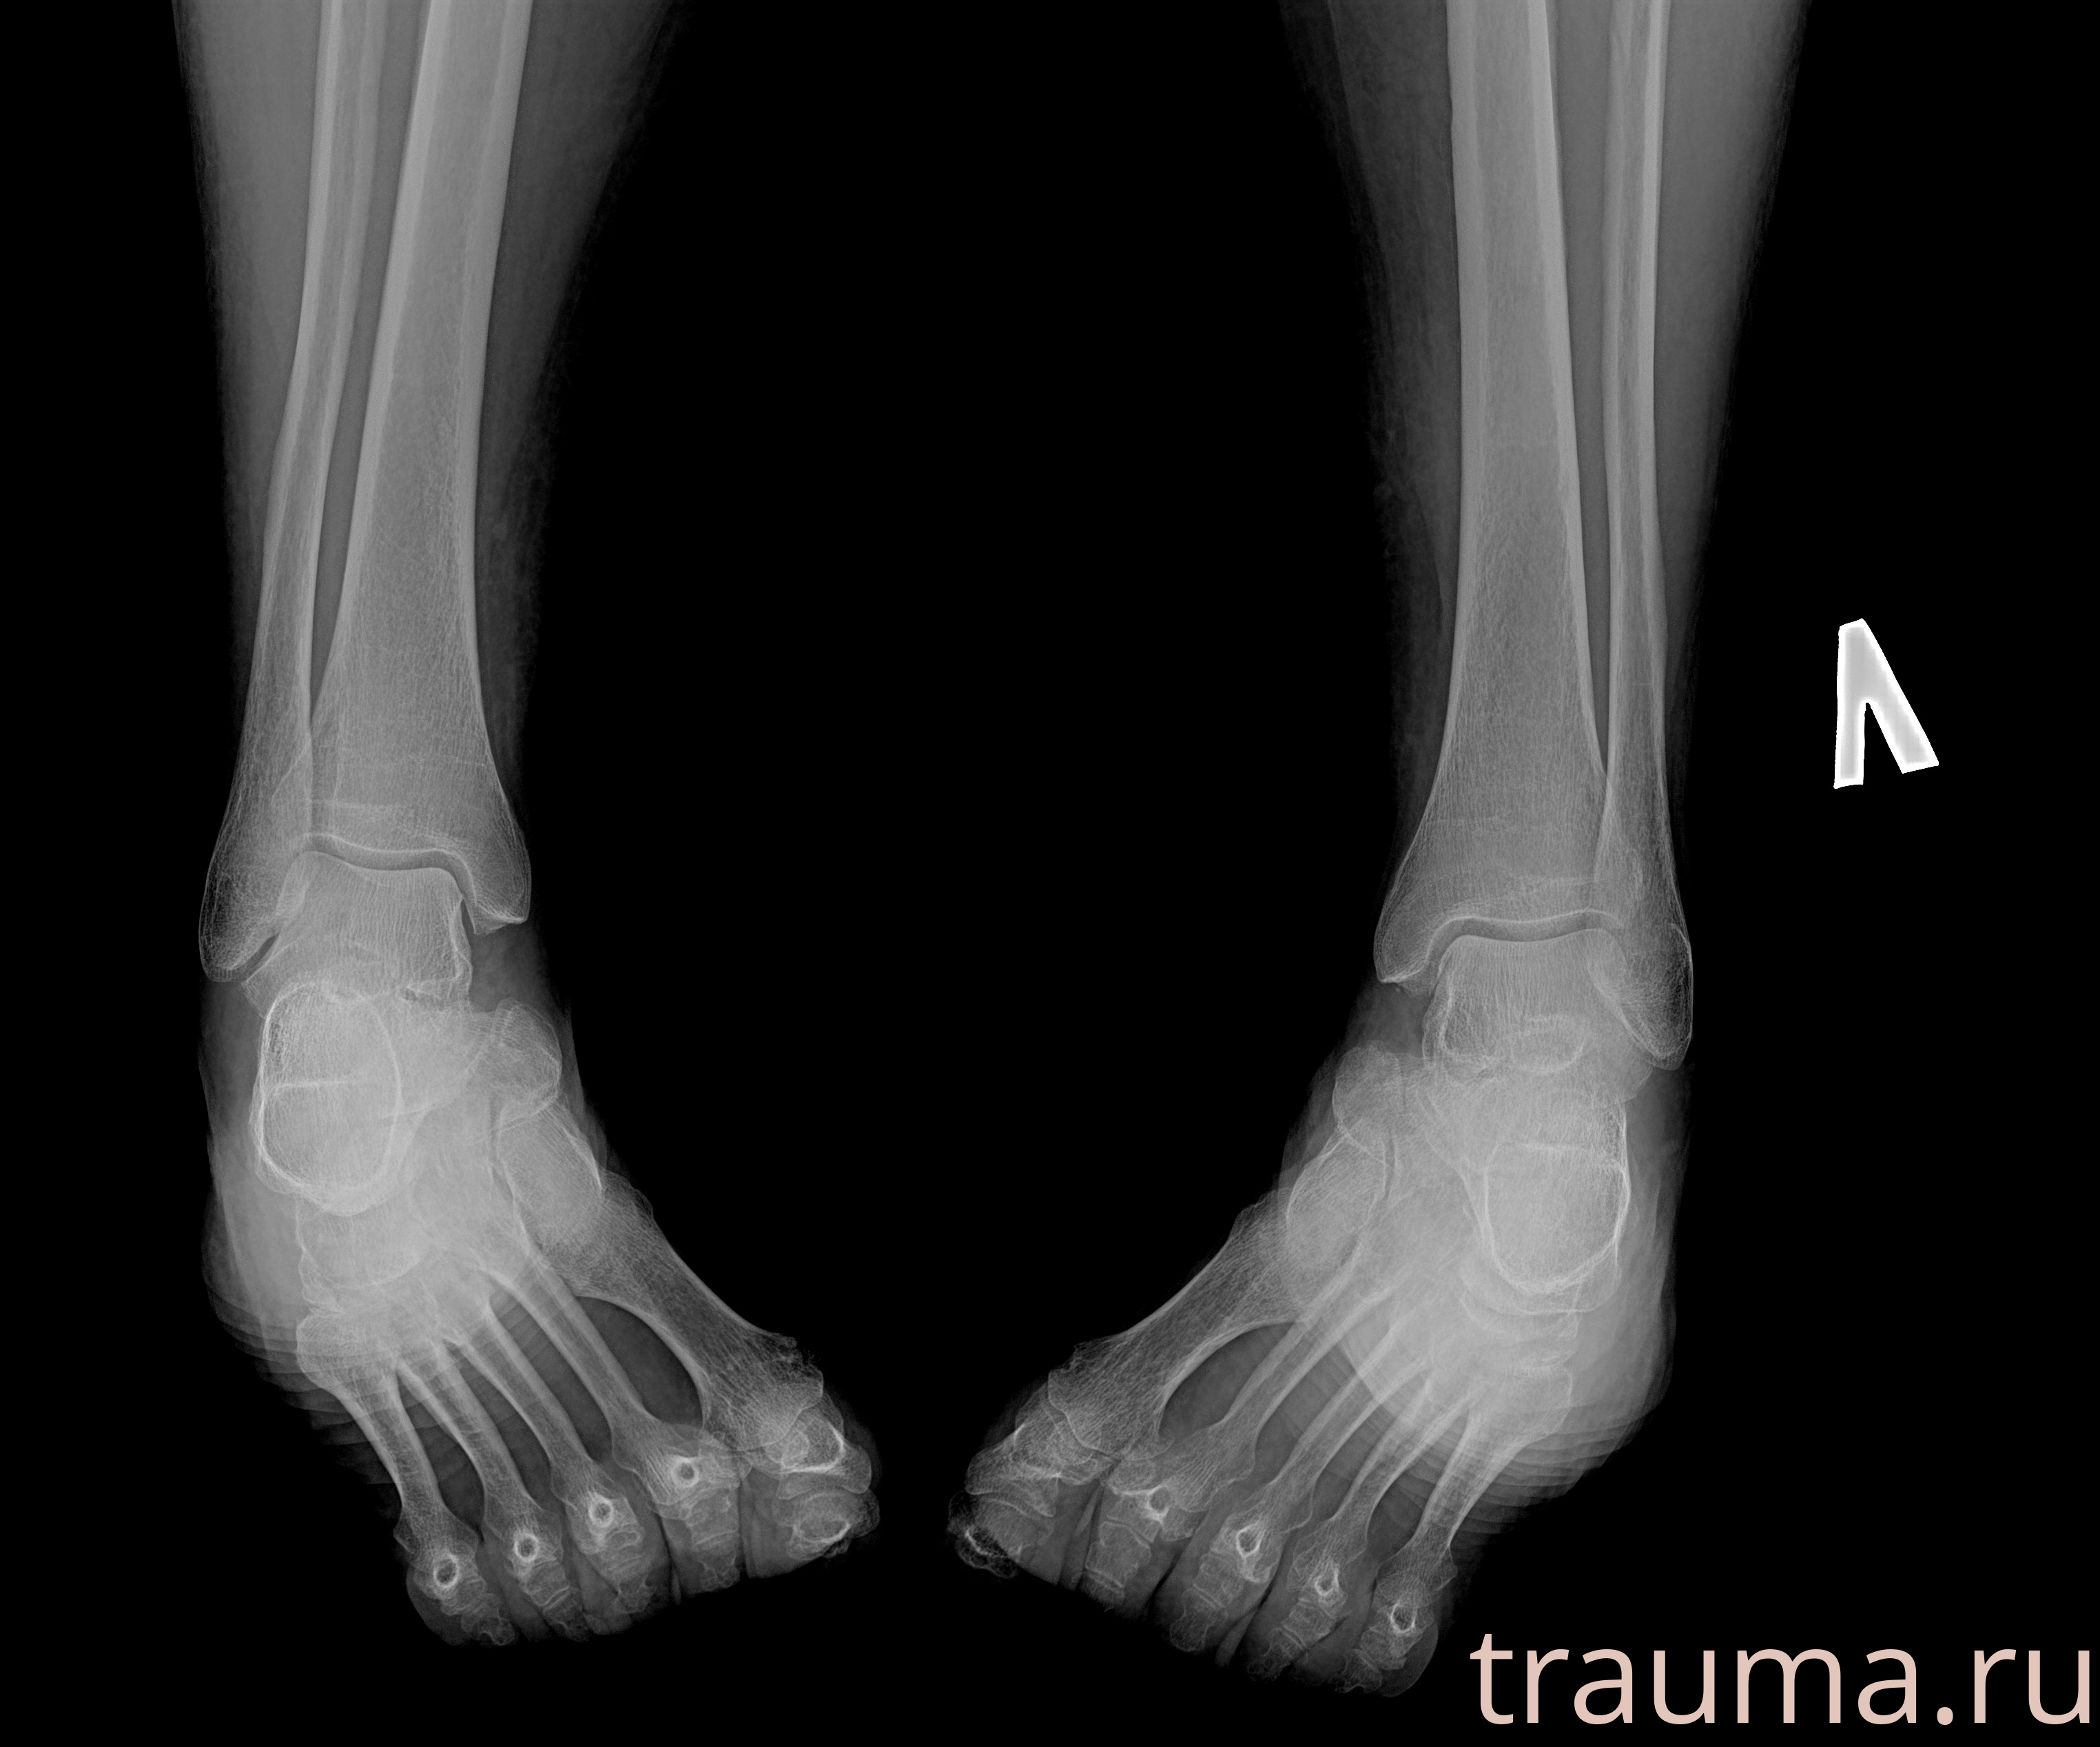

Рентгенограммы

Рентген на дому: по вашему адресу приезжает врач-рентгенолог, травматолог-ортопед с мобильным рентгеновским аппаратом, проводит диагностику травмы или заболевания, делает необходимые рентгенограммы, дает рекомендации по дальнейшему лечению. Получить качественные снимки в домашних условиях возможно благодаря уникальной методике, разработанной МосРентген Центром для института  Склифосовского